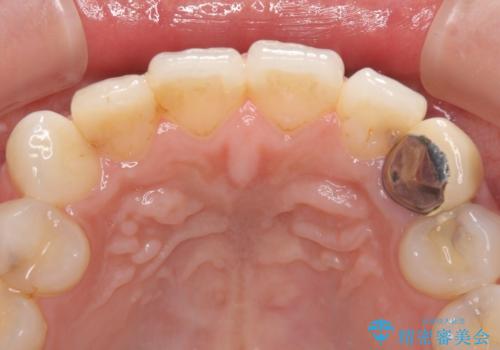

- 前歯の保険のかぶせものをセラミックに替えたいと来院された患者様です。

保険のかぶせもの特有の変色や縁の金属色、歯根が一部見えている点が気になるとのことでした。

土台の金属を除去してファイバーコアによる土台植立を行い、オールセラミッククラウンにて補綴することとしました。